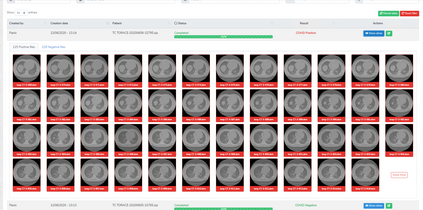

COVID-19 infection caused by SARS-CoV-2 pathogen is a catastrophic pandemic outbreak all over the world with exponential increasing of confirmed cases and, unfortunately, deaths. In this work we propose an AI-powered pipeline, based on the deep-learning paradigm, for automated COVID-19 detection and lesion categorization from CT scans. We first propose a new segmentation module aimed at identifying automatically lung parenchyma and lobes. Next, we combined such segmentation network with classification networks for COVID-19 identification and lesion categorization. We compare the obtained classification results with those obtained by three expert radiologists on a dataset consisting of 162 CT scans. Results showed a sensitivity of 90\% and a specificity of 93.5% for COVID-19 detection, outperforming those yielded by the expert radiologists, and an average lesion categorization accuracy of over 84%. Results also show that a significant role is played by prior lung and lobe segmentation that allowed us to enhance performance by over 20 percent points. The interpretation of the trained AI models, moreover, reveals that the most significant areas for supporting the decision on COVID-19 identification are consistent with the lesions clinically associated to the virus, i.e., crazy paving, consolidation and ground glass. This means that the artificial models are able to discriminate a positive patient from a negative one (both controls and patients with interstitial pneumonia tested negative to COVID) by evaluating the presence of those lesions into CT scans. Finally, the AI models are integrated into a user-friendly GUI to support AI explainability for radiologists, which is publicly available at http://perceivelab.com/covid-ai.